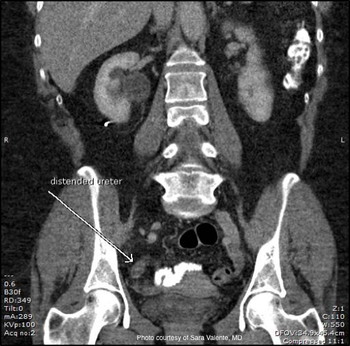

An elderly male with hypertension, lumbar spinal stenosis, morbid obesity, and ED presents with acute right-sided worsening of his chronic back pain. A distal right ureteral stone is found on CT and his symptoms respond well to medical therapy, but he later develops severe right flank pain.

A 61-year-old female complains of acute-onset right-sided flank and abdominal pain. She describes associated nausea, but denied urinary symptoms, hematuria, fever, or chills.